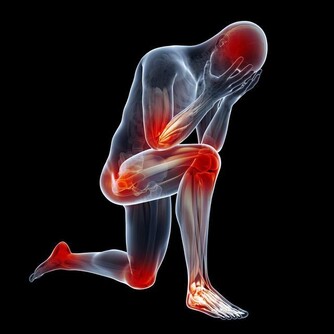

痛風:洋蔥泡紅酒

洋蔥去皮切開泡紅酒,放在冰箱冷藏一周,飲用吃蔥,對痛風也很有幫助。